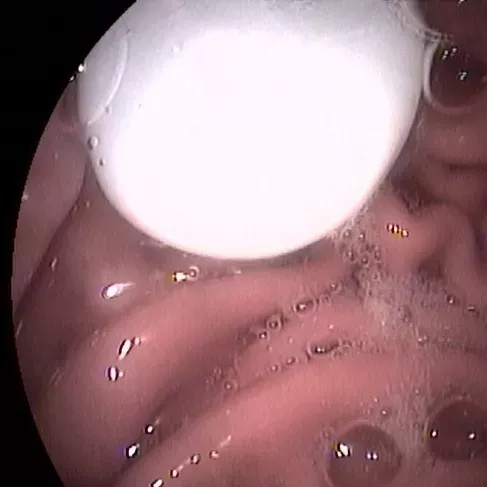

小编再带您看看这些年我院胃肠镜室从孩子身体里取出过的异物,对照一下,您家孩子接触过几样?

五子棋